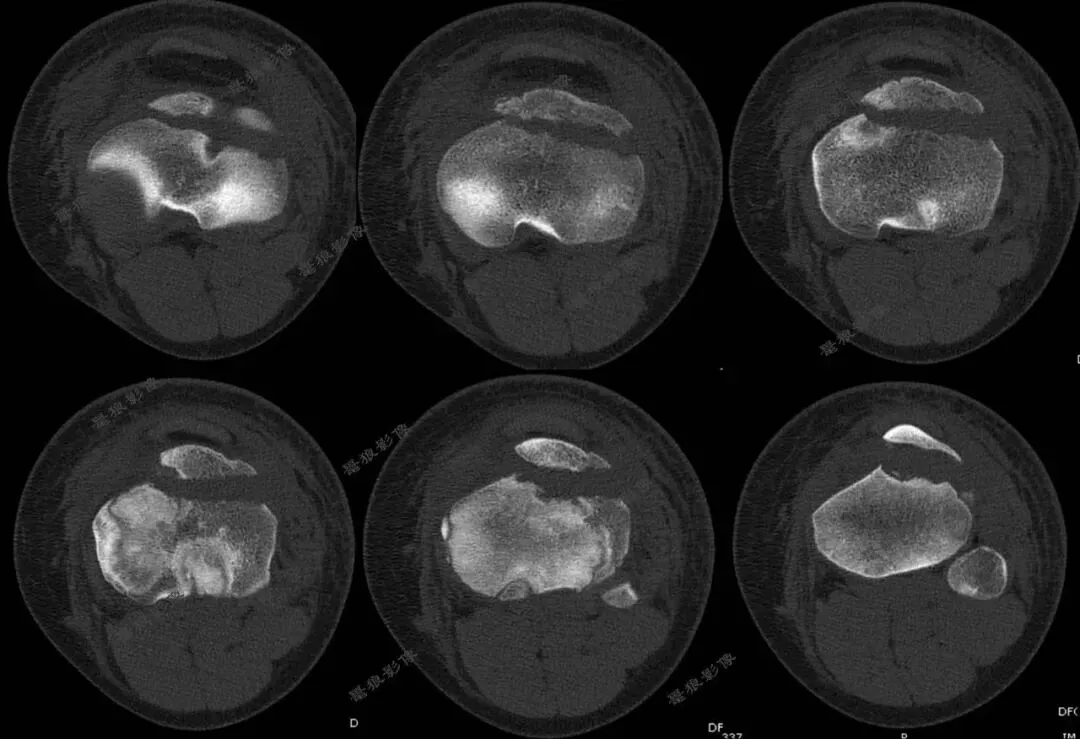

二.术前CT

胫骨结节骨折(OgdenIIIA型 )

4.术后CT:

一.任一提示 Ogden II型 及以上的骨折,应高度警惕骨折累及关节内延伸与后方干骺端成分,推荐CT进行三维重建和软组织评估,必要时联合MR检查。

二.胫骨结节骨折以骨折线走行、骺板及关节面受累情况,以及骨折移位、粉碎程度为核心,直接关联是否需要手术、术式复杂度和并发症风险。